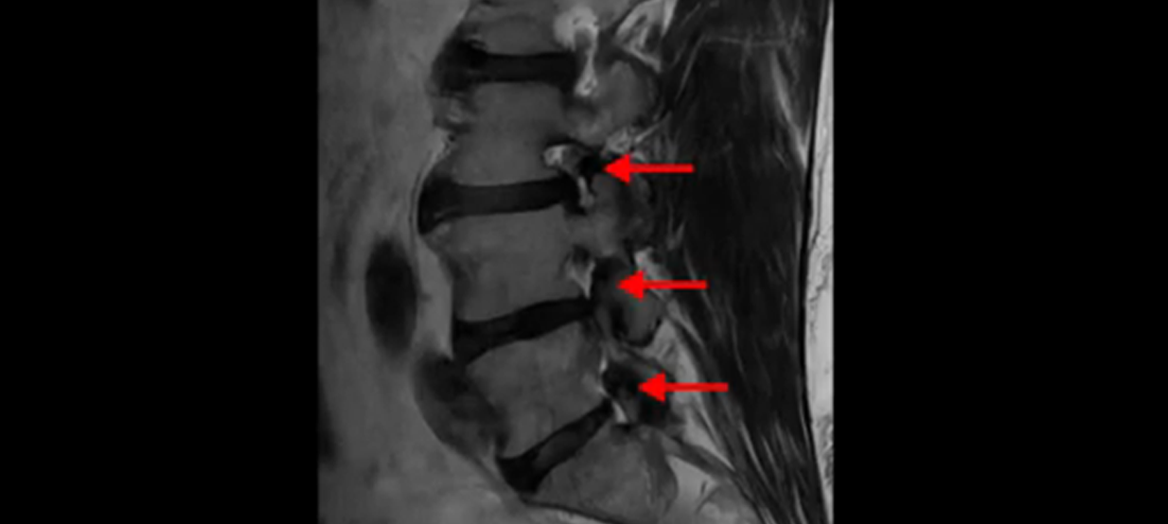

또 왼쪽 신경 가지들이 빠져 나가는 신경구멍들이 여러 마디가 좁아져 있습니다.

이런 이유들 때문에 왼쪽 엉덩이부터 종아리, 발가락까지 저리고 아픈 겁니다. 그래서 서둘러 병원에 가셨는데요. 그래서 서둘러 병원에 가셨는데요. 여러분이 꼭 아셔야 할 게 이렇게 다리가 심하게 저리고 아프면 X-ray만 찍을 게 아니고 MRI를 찍어 보시는 게 맞습니다. X-ray로는 디스크가 터졌는지 신경구멍이 좁아진 협착이 있는지를 정확히 할 수가 없습니다. 그래서 이분은 당장 아픈데 해결이 안 되니까 제주도에서 유명하다는 한의원으로 갔습니다.